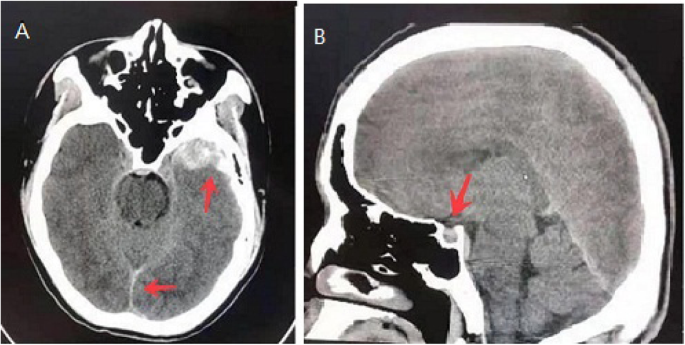

A 70-year-old female patient with a one-year history of diabetes insipidus was transferred to the Emergency Department of our hospital due to confusion and hypotension (minimum of 70/44 mmHg, maintained by dopamine). She also had fever (maximum of 39.3 °C), chills, and cough with a small amount of white phlegm that lasted for 2 days. The patient fainted 6 months ago and fell, and the head computed tomography (CT) at that time demonstrated left frontal and occipital fractures accompanied by frontotemporal lobe cerebral contusion, subarachnoid and subdural haemorrhage (Fig. 1 a), and incidental pituitary micro adenoma (Fig. 1 b). She had menopause at 48 years old.

In this study, we report the first case of Takotsubo cardiomyopathy with hypopituitarism in the setting of pituitary apoplexy and provide evidence to support that pituitary apoplexy may be associated with myocardial stunning. The old woman suffered diabetes insipidus that may be related to prior head trauma, and cranial CT at that time revealed subarachnoid and subdural haemorrhage and pituitary micro adenoma. However, her admission investigations showed that she had decreased sex hormones, thyroid hormones and ACTH levels, hypouria, increased urine volume, and reduced electrolyte levels, suggesting that both anterior hypophysis and neurohypophysis functions were affected. The patient had suffered significant stressor such as fever and pulmonary infection before the onset of the symptoms and had emergency signs and symptoms such as hypotension and unconsciousness at the presentation, all of which conform to acute pituitary apoplexy.